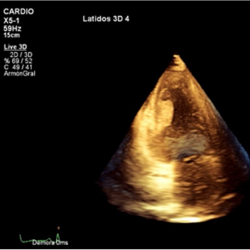

3D-transthoracic echocardiogram. Apical two-chamber view. Mass attached to the left ventricular inferior wall.

Conventional transthoracic echocardiography was repeated a week later, without changes. 2D-echocardiographic study was completed with intravenous echocardiographic contrast to demonstrate perfusion of the mass, excluding the diagnosis of thrombus (Movie II in the Data supplement) and with 3D echocardiography for better visualization and establishing spatial relationships of the mass (Movie III and Movie IV in the data supplement).